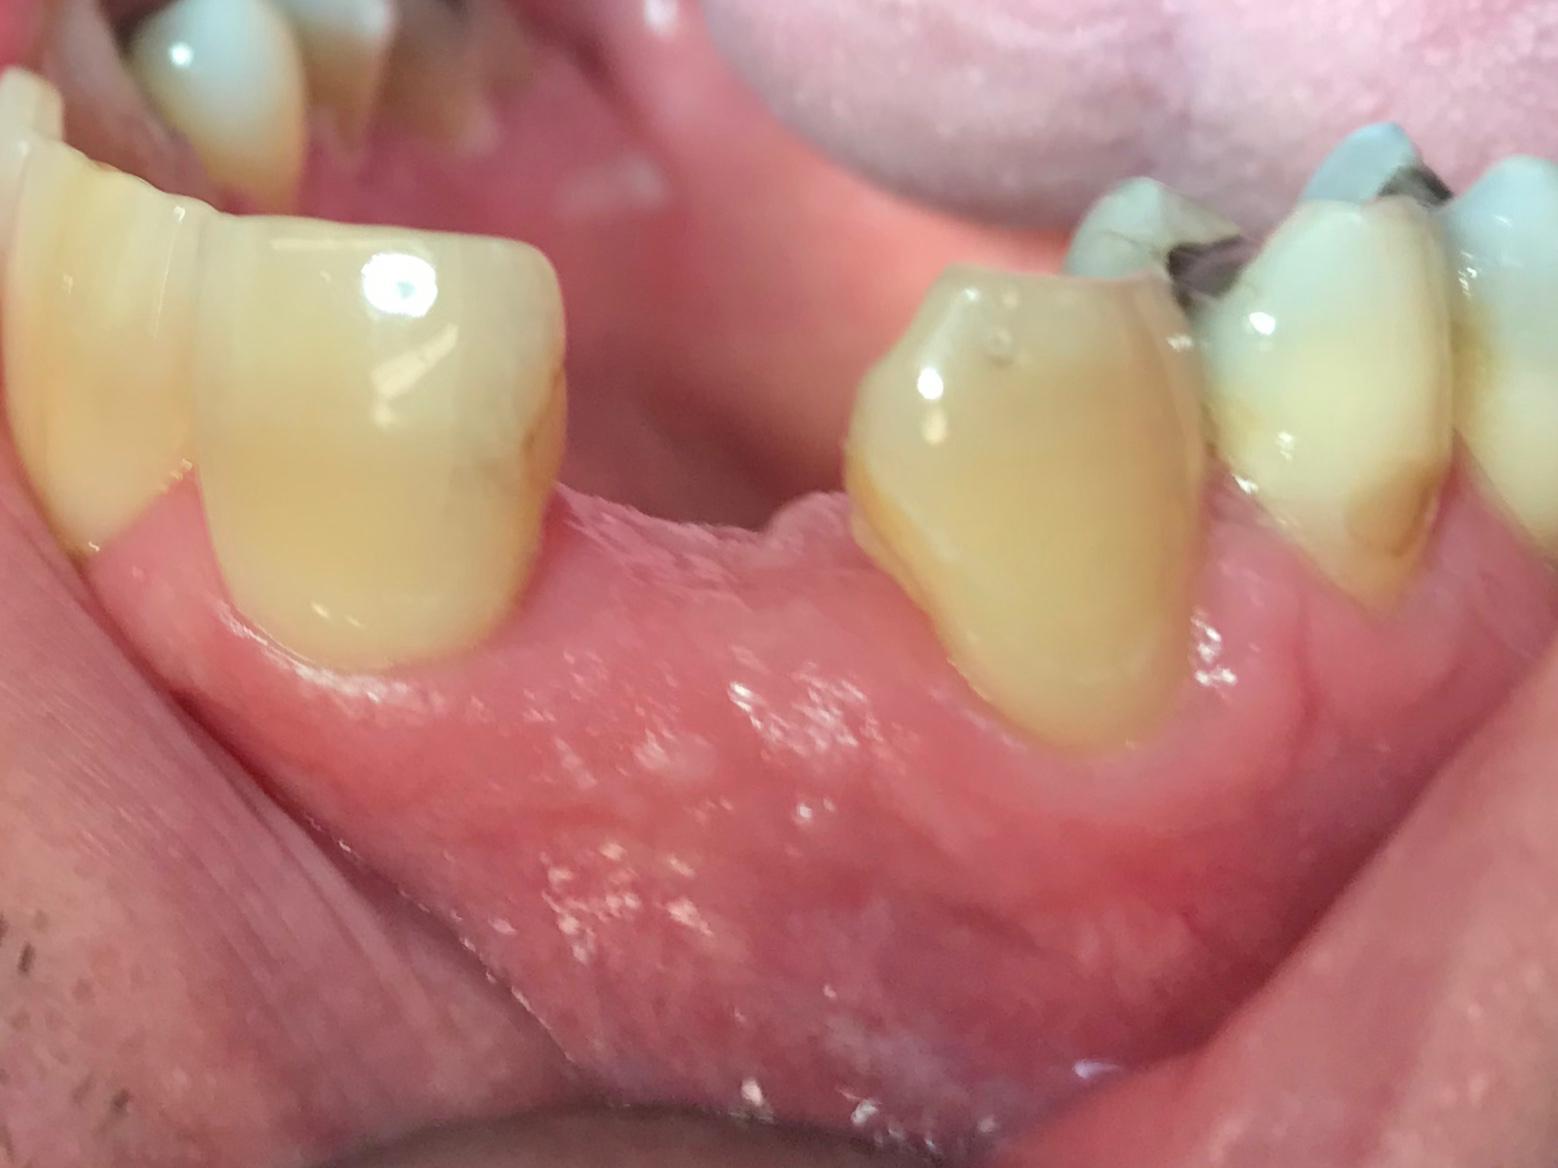

Immediate implant placement with simultaneous bone augmentation and connective tissue grafting. The case will be completed with crown lengthening, veneer replacement, and soft tissue optimisation to achieve ideal emergence profiles.